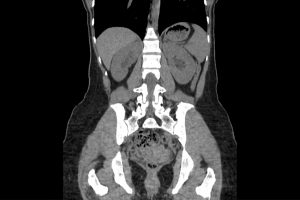

MRI Guided Volume Based Outpatient Brachytherapy

HOW IT WORKS: Internal radiation using MRI for precise tumor targeting.

WHAT IT IS USED FOR: Cervical cancer and pelvic tumors.

WHAT TO EXPECT: Outpatient; applicators placed under anesthesia; MRI before each dose; mild discomfort.